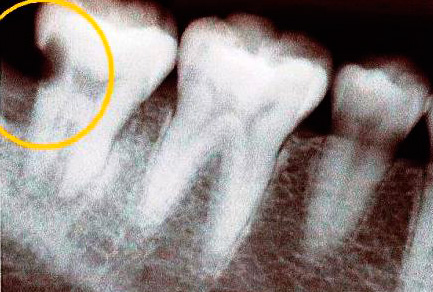

La foto sotto mostra la carie nascosta nel dente estratto (situato sulla superficie di contatto, cioè nel punto di contatto con il dente adiacente). L'area interessata ha raggiunto la camera pulpare: